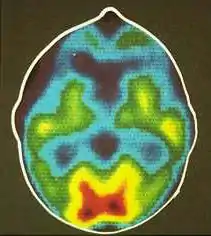

- اسکن مغزی: تزریق موادی پرتوزا، عبور آن از سد خونی مغز، تجمع آن در آسیبدیدگیهای مغزی (مثل تومورها)، و تصویربرداری و تشخیص آن توسط یکی از روشهای تصویربرداری.

- پت اسکن و اسپکت

تصویرسازی مولکولی در سالهای اخیر چنان در بیمارستانها و مراکز درمانی رواج پیدا کرده که اکنون این روشها خود دارای بخش جداگانهای در پزشکی هستهای میباشد. متعارفترین روشهای تصویرسازی مولکولی عبارتند از پت اسکن و اسپکت.